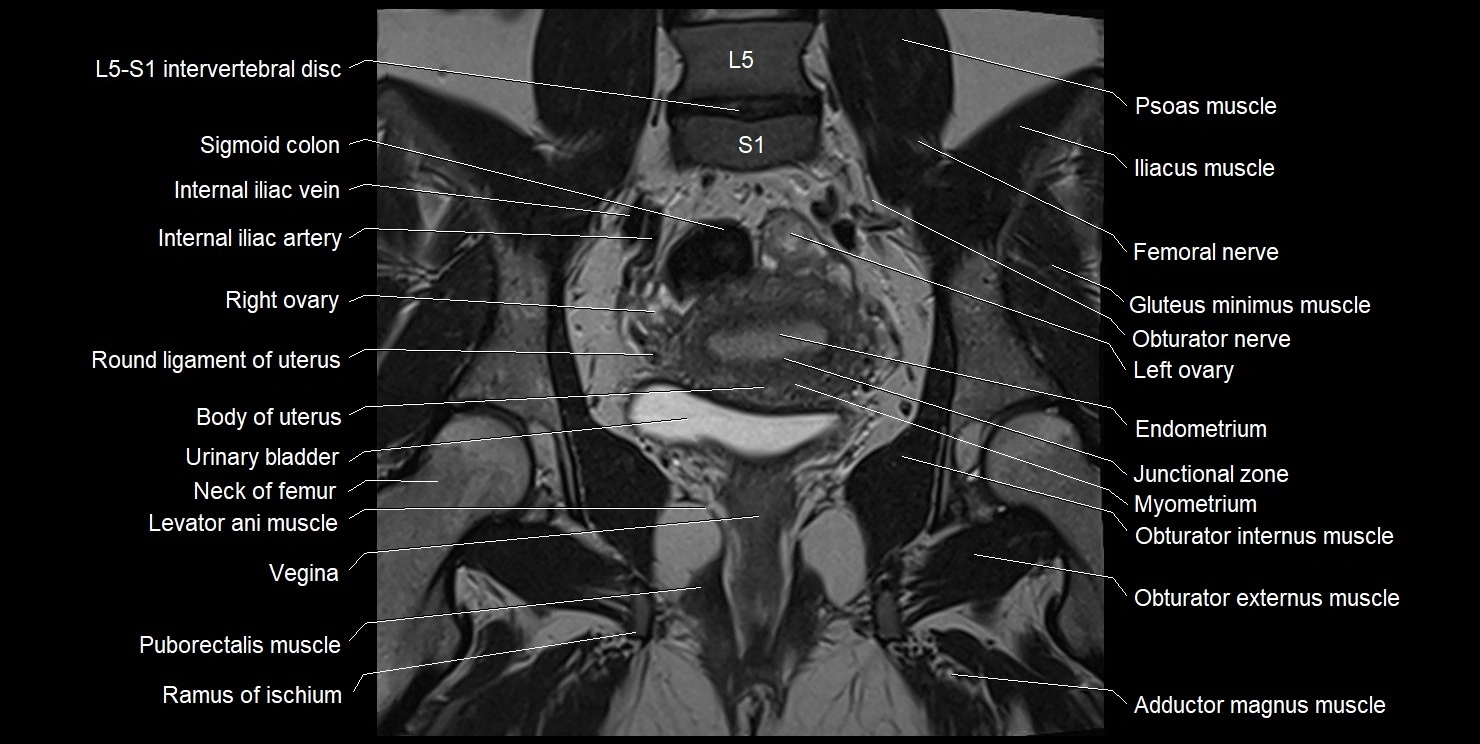

- Body of uterus

- Endometrium of uterus

- Femoral nerve

- Fundus of uterus

- Gluteus minimus muscle

- Iliopsoas muscle

- Internal iliac artery

- Internal iliac vein

- Junctional zone of uterus

- L5–S1 Intervertebral disc

- Left ovary

- Levator ani muscle

- Myometrium of uterus

- Neck of femur

- Obturator externus muscle

- Obturator internus muscle

- Obturator nerve

- Psoas major muscle

- Pubic symphysis

- Puborectalis muscle

- Ramus of ischium

- Rectum

- Right ovary

- Round ligament of uterus

- Sigmoid colon

- Urinary bladder

- Vagina